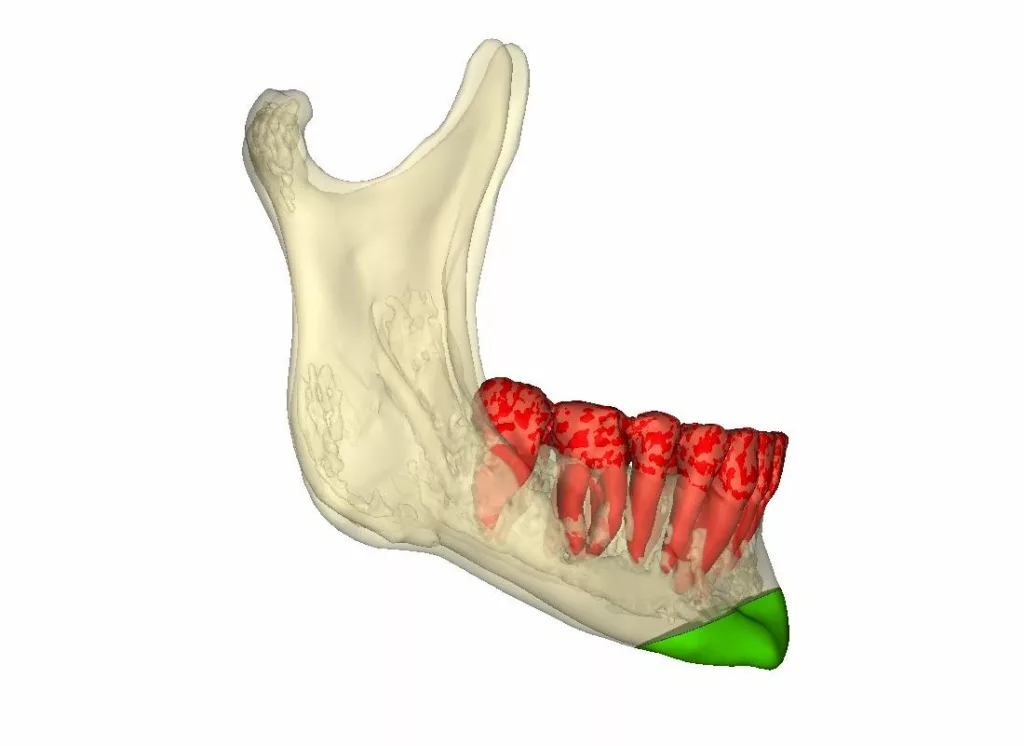

L’ostéotomie sagittale des branches montantes

Elle permet de déplacer l’ensemble de l’arc denté mandibulaire c’est à dire ensemble de « os basal – os alvéolaire – dents inférieures » dans les trois dimensions de l’espace.

La « décompensation» vise à annuler ou à diminuer les compensations subies par l’os alvéolaire en cas de malformation. Ces compensations peuvent être spontanées ; naturelles (« la nature » s’adapte pour diminuer les effets de la malformation sur l’occlusion) ou provoquées (un traitement orthodontique a été réalisé préalablement pour corriger ou diminuer le trouble de l’occlusion créé par la malformation).

En pratique, la décompensation alvéolaire orthodontique préchirugicale consiste à supprimer les compensations sur l’os alvéolaire avant l’intervention afin que le traitement chirurgical sur les bases osseuses soit aussi efficace que possible. Les décompensations pré-chirurgicales s’accompagnent souvent d’une aggravation de l’anomalie initiale de occlusion. Le patient en est informé.